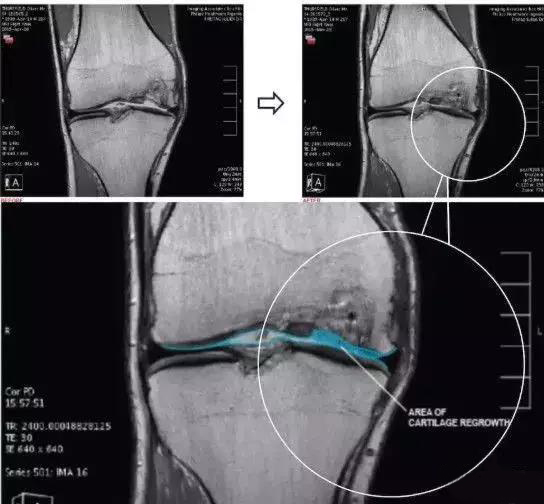

墨尔本干细胞治疗中心利用患者自身的间充质干细胞注入膝关节治疗膝关节损伤的临床研究是全球范围都较为知名的一项临床试验,这个试验共涉及70名患者,分为30名一组进行对照。最终结果显示,大部分参与试验的患者膝关节功能有了很大的改善:三分之二的患者膝盖疼痛程度和活动受限程度减少了一半,并且保持了一年以上。

2016年,曾在《干细胞转换医学杂志STEM CELLS TRANSLATIONAL MEDICINE》上报道过,在中外学者共同参与的一项研究中,用人自身来源的软骨细胞结合生物胶原支架,治疗软骨缺损,治疗后随访12个月全部患者的临床评分得到了提高,功能得到改善,疼痛得到缓解。

术后第二次关节镜检查(图a)。在所有4名患者中,移植区域具有保存完好的透明状软骨结构。4例活检标本的组织学检查结果表明,与邻近关节炎软骨相比,修复效果更好。组织显示存在软骨细胞样细胞,以及透明软骨样结构和基质。所有四个活检标本均为无异位钙化和血管化。并且没有发现炎症迹象。

上图a为治疗前关节镜检查结果,可以看出软骨存在缺损。图b为脂肪间充质干细胞联合PRP治疗,图c为治疗后结果,软骨得到了修复。

在一部来自Youtube上的视频中,医生采集患者自身外周血中的干细胞,联合PRP(富血小板血浆)治疗关节病,患者自述这种疗法有效缓解了疼痛,提高了生活质量。

由此可见,在关节疾病治疗方面,干细胞技术在近年来引起广泛关注。越来越多的临床数据显示,干细胞可以作为一种有效的手段,完美地补足现有治疗方法的缺陷,人们对以干细胞为基础的关节疾病再生治疗有着不断增长的需求,期待以干细胞为基础的治疗在骨科领域得到广泛应用。